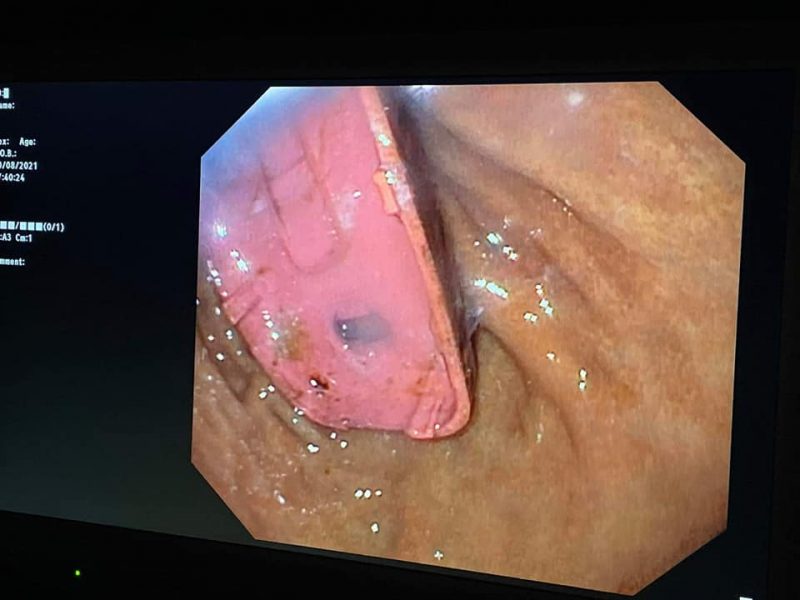

“Ata më thirrën për një rast, ishte një person që kishte gëlltit një trup të huaj, u desht të bëhet gastroskopia me urgjencë, kur hynëm në lukth e pam që ishte telefoni i ndarë në pjesë tri pjesë. Një pjesë ishte kapaku i përparshëm dhe i pasmi i plastikës, plus bateria brenda. Hyjmë me pajiset që i kemi këtu, njëherë e nxorëm një pjesë, mandej pjesën tjetër, në fund e nxorëm edhe baterinë, nga të gjitha këto pjesë bateria është më e rrezikshmja sepse ajo pjesë ishte ajur dhe mund të shpërthejë. Mund të lëshojë materie kimike dhe mund t’i shpërthejë zorrët”, tha Teleku për Gazetën Express.

“Ky nuk është operacion, është rrugë endoskopike, nga goja e kemi nxjerrë, sikur të mos kishim sukses do të duhej me pre barkun dhe me nxjerrë nga barku. Jemi mundu dy orë dhe u nxorr”.

Pamje të telefonit që qëndroi katër ditë në stomakun e pacientit ka publikuar doktor Skender Telaku.

“Mashkulli 33 vjec para 4 ditesh kishte perbire nje telefon te vogel. Me rruge endoskopike, pra pa e prere lukthin, nxorrem telefonin e ndare ne tri pjese. Pa komplikime”, ka shkruar ai.